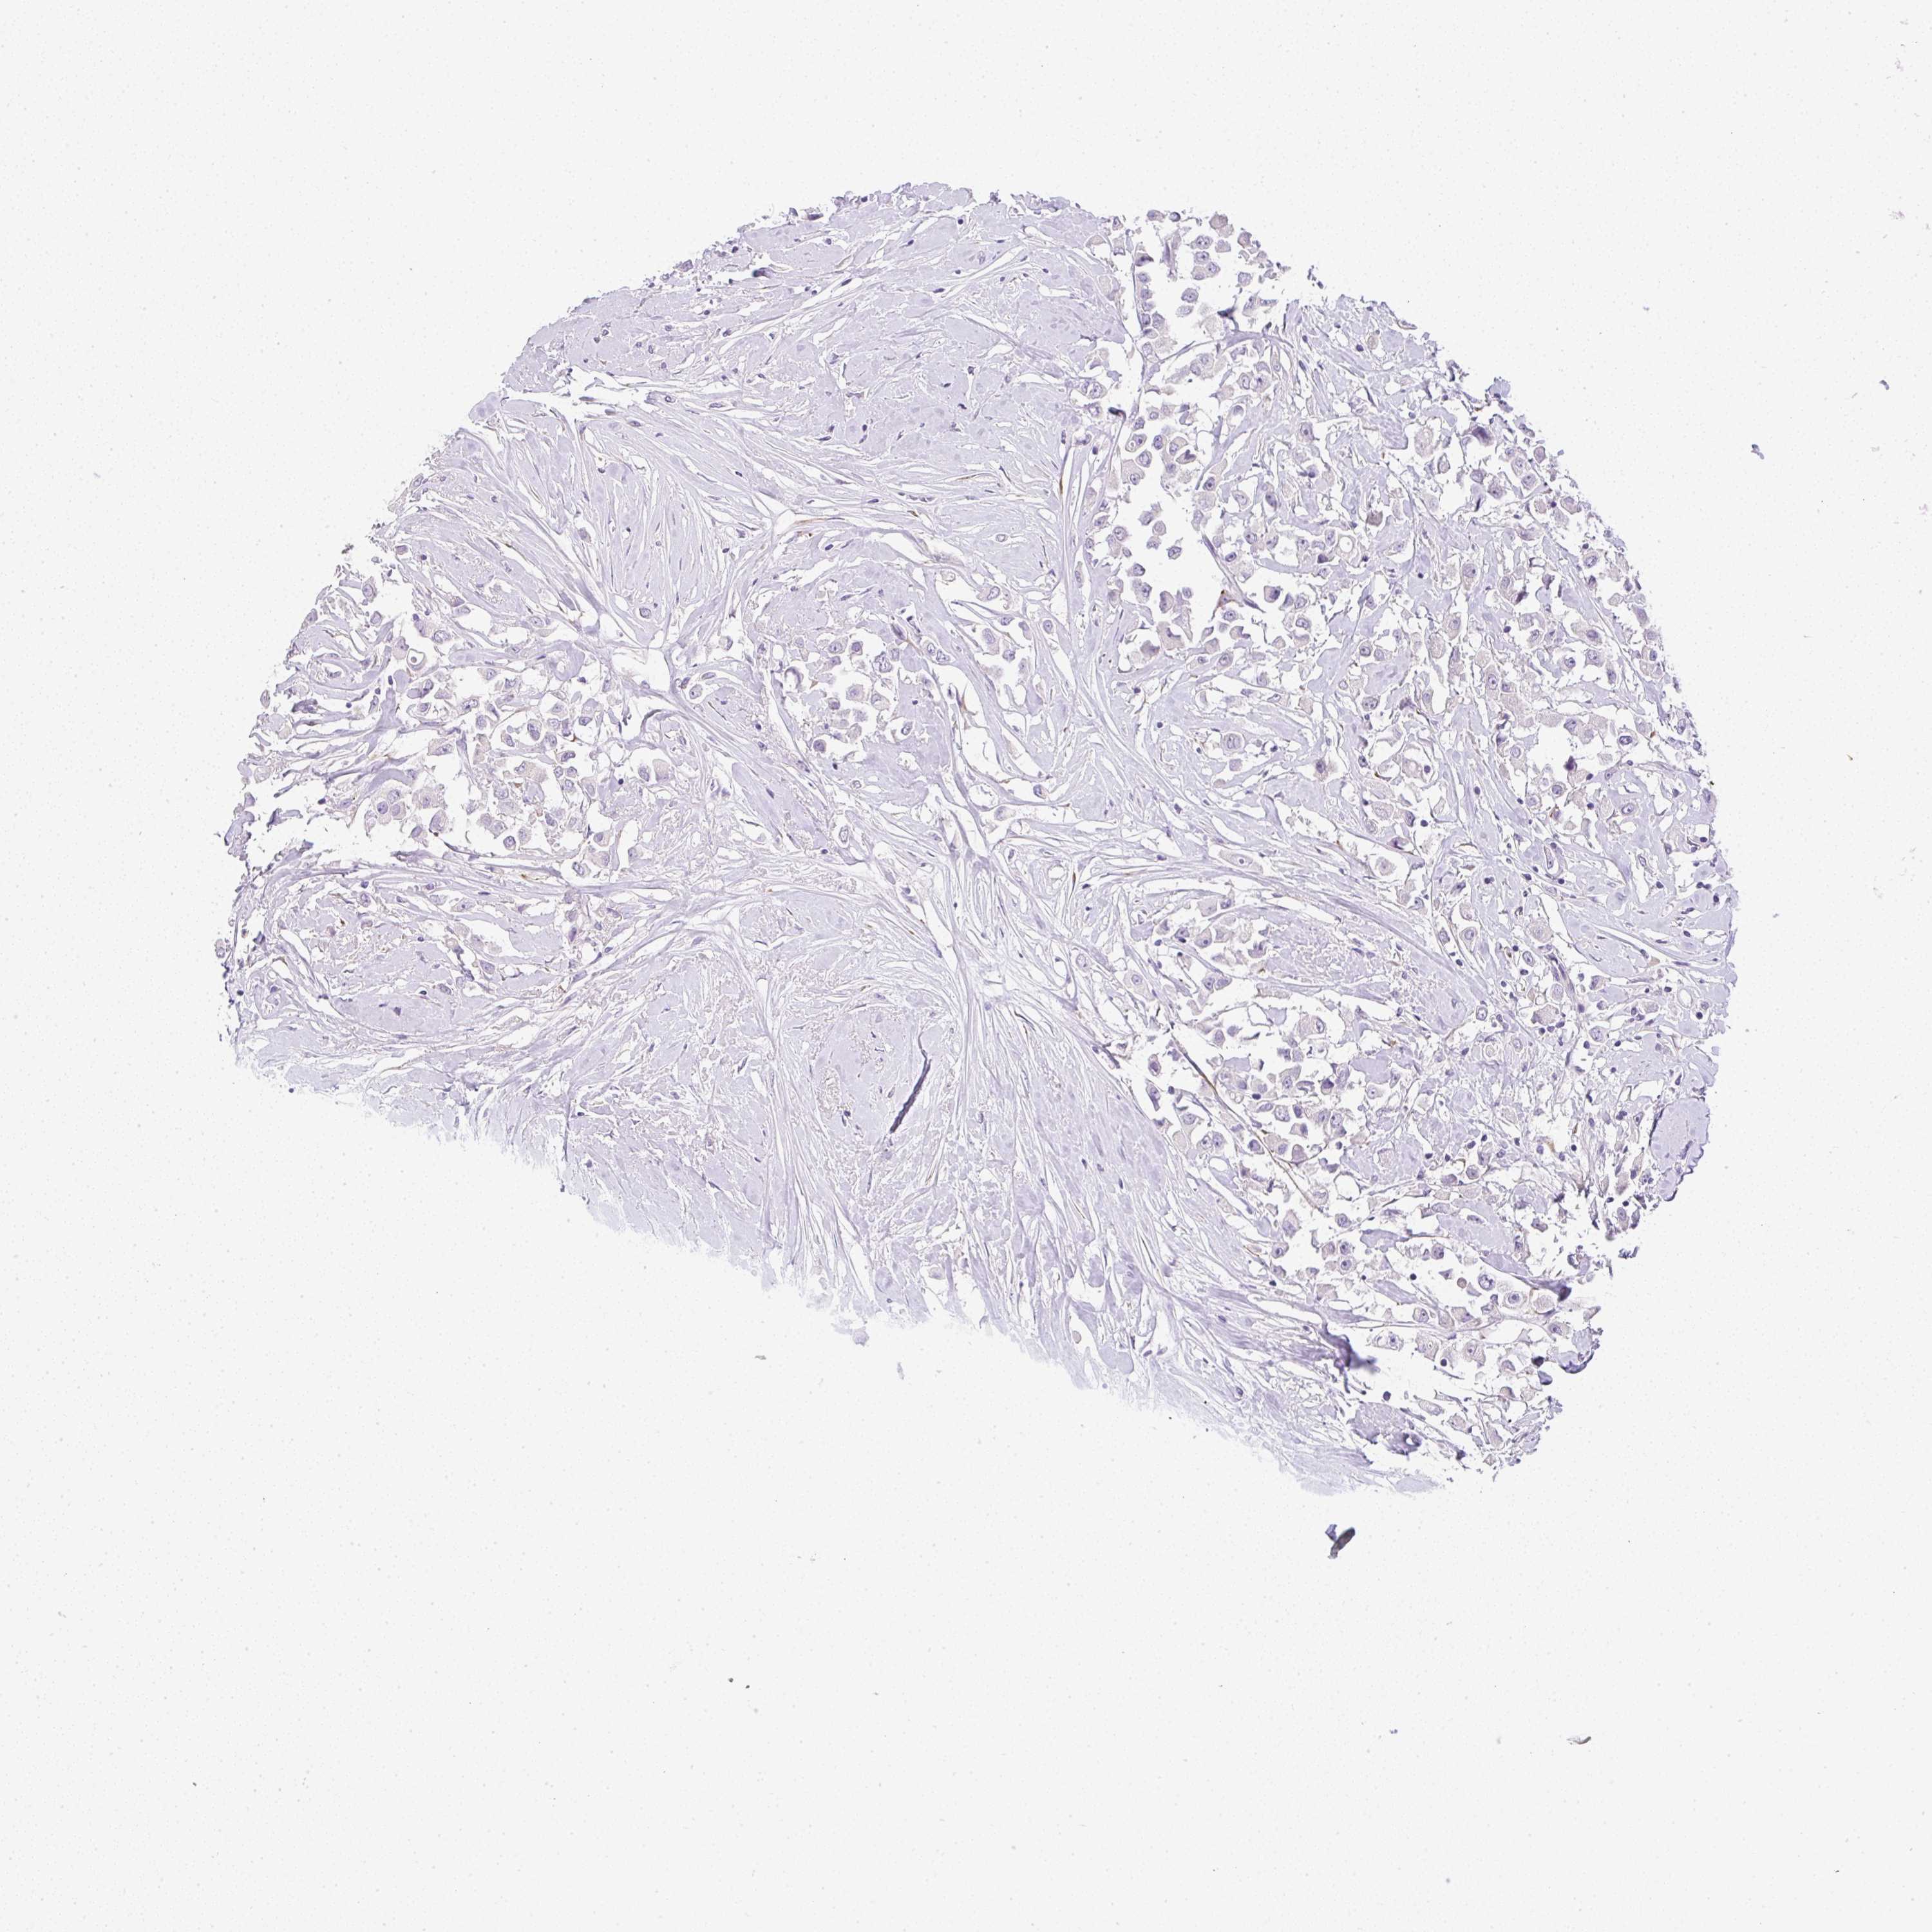

BRCA TCGA BRCA VALIDATION PROTEIN EXPRESSION

ANTIBODIES

AND

VALIDATION